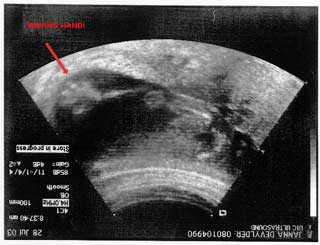

The best part of the session came about when we were trying to get the baby to stay still for at least one face shot. Every time we would get close, he would flip all around. Not cooperative. Finally, I tapped on my belly and said, "HELLO??" and suddenly we saw a sole hand on the screen, waving back and forth. We all just went wild, it was such a crazy occurance. See his hand?